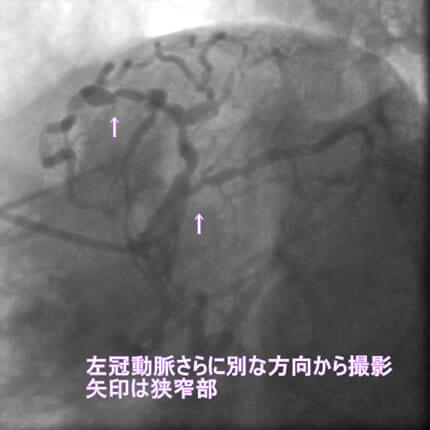

1番目の患者さんは80歳の男性です。この方の危険因子は高血圧、高脂血症、喫煙です。この方の冠動脈造影と腹部CT画像を示します。図1-1から1-8の画像は全て全てこの患者さんの画像です。

図1-4 左冠動脈造影像

よく解らないと思いますが、冠動脈に多数の狭窄があることと冠動脈が「こぶ状変化(医学用語で瘤状変化)」を生じているのが解ると思います。